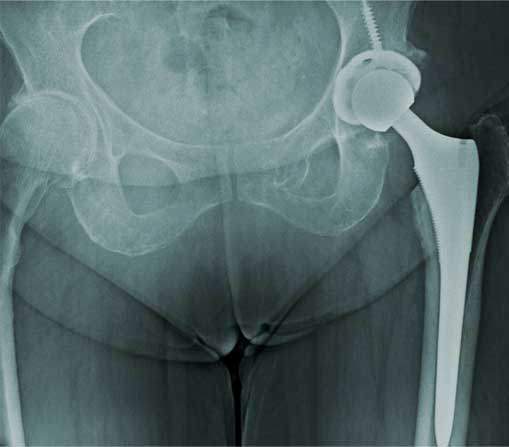

Prótesis de cadera

Es también conocida como reemplazo de cadera, la cual consiste en la sustitución de la articulación dañada o un implante de metal, cerámica o plástico que realiza la función de la articulación, mejorando el dolor.

Las indicaciones más comunes son la artrosis o desgaste de cadera en adultos mayores, otras indicaciones son las fracturas de cadera, el daño crónico o infección, artritis reumatoide, secuelas de enfermedades de la cadera o traumatismos, las cuales se presentan en adultos jóvenes y adultos mayores.

El paciente puede caminar desde el mismo día de la cirugía, se da de alta a su domicilio a las 24 horas y puede realizar actividades cotidianas en casa de forma autónoma desde la primera semana. La recuperación parte en un 80% de la función de la cadera en el primer mes, 90% de la función en el segundo mes y 92% - 98% de la función en el tercer mes.

Eliminar el dolor en la zona afectada, mejorar la función como es fuerza muscular, movimiento, estbilidad y biomecánica, logrando mejorar la calidad de vida del paciente.